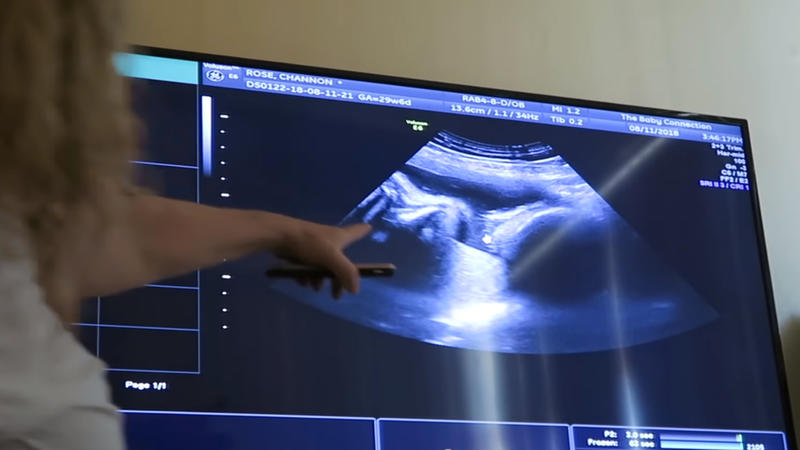

The pregnancy was unique for Katie, her husband, as well as the doctors who were taking care of Katie. But, you’ve guessed it! Katie and Angelo couldn’t be happier to find out something in their lives. They were ecstatic to learn that Katie was carrying triplets. They were delighted to grow their family as much as they could. They were going with “the more, the merrier” philosophy. Having three more kids to look after wasn’t a big challenge for the couple. Or at least that was what they thought!